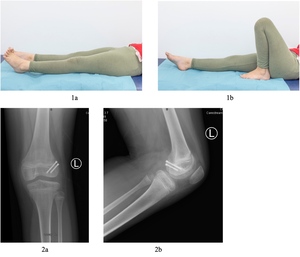

A 7-year-old girl sustained an injury to the left knee after falling off her bicycle. She described the trauma mechanism as a direct impact to the anterior aspect of the knee with the knee in a semi-flexed position. She experienced immediate swelling of the knee but was able to bear weight. The patient presented to the emergency room five days post injury due to persistent knee swelling and an inability to fully extend her knee.

Clinical examination of the left knee revealed a large knee effusion associated with a restricted range of motion (ROM). There was a FFD of 40° and a flexion of 90°. Straight leg raise was intact, but she had a significant extensor lag. The lateral joint line was tender on palpation. Hip and ankle examination of the ipsilateral side was normal. While she was able to weight bear her gait was severely impacted.

Initial lateral knee plain radiograph confirmed a large joint effusion with what looks like an associated rim of calcification posteriorly, while the anteroposterior (AP) radiograph was essentially normal with only subtle calcification around the lateral femoral condyle. (Fig 2)